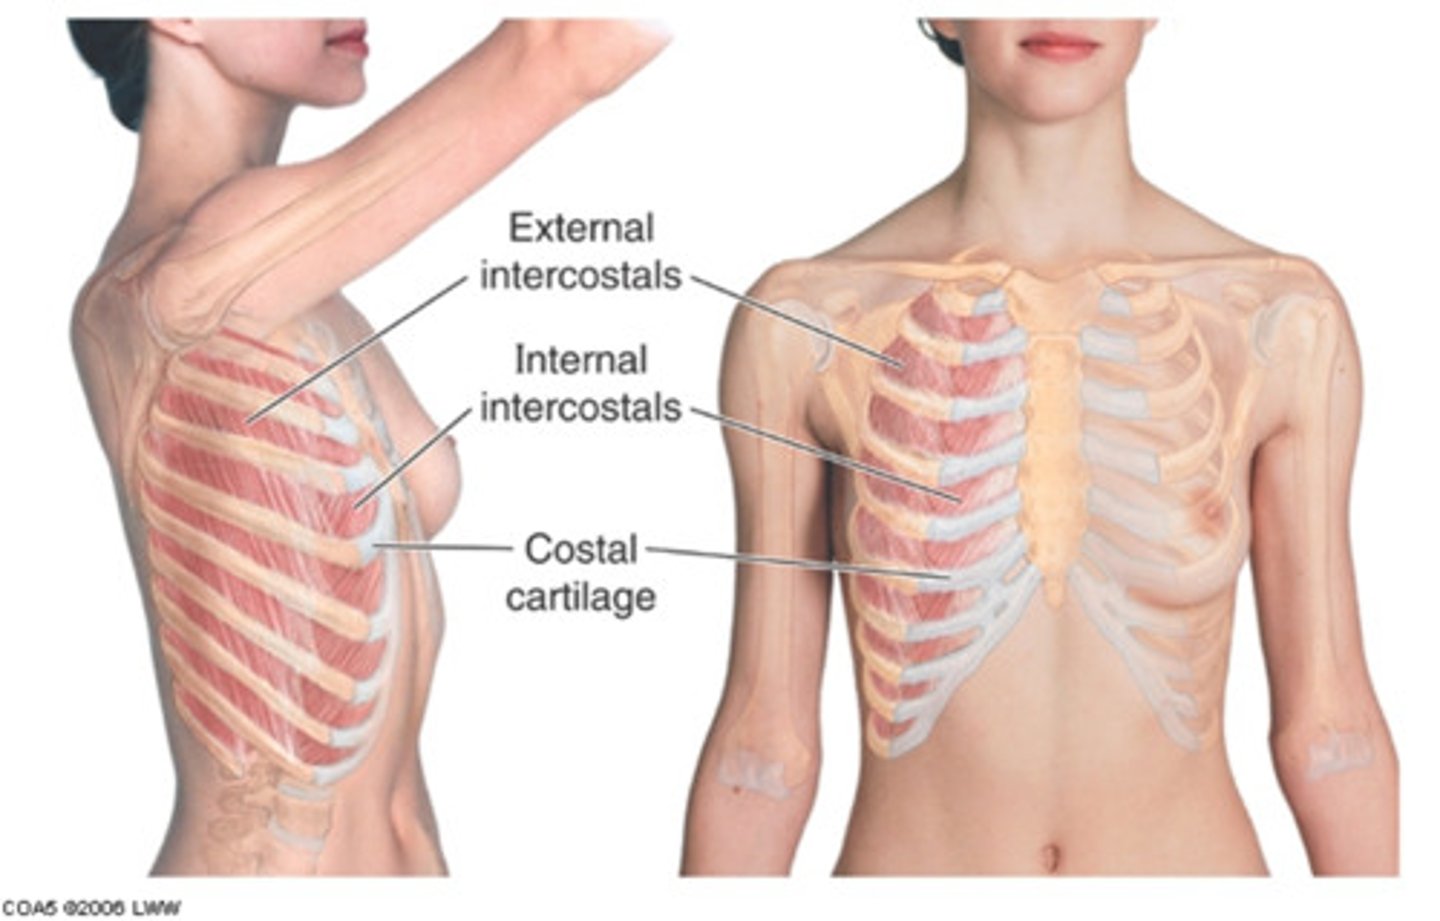

What makes up the thoracic cage?

sternum, ribs, and thoracic vertebrae

What is the function of the thoracic cage?

Protects heart, lungs, trachea, esophagus, and other thoracic organs, support upper limbs and provide muscle attachments

ribs, sternum, thoracic vertebrae, encloses organs and moves for ventilation

thoracic wall

thoracic cage, skin, subcutaneous tissue, fascia, IC muscles

How is the costal cartilage numbered?

by the rib it articulates with

How are intercostal spaces numbered?

According to the rib superior to the space